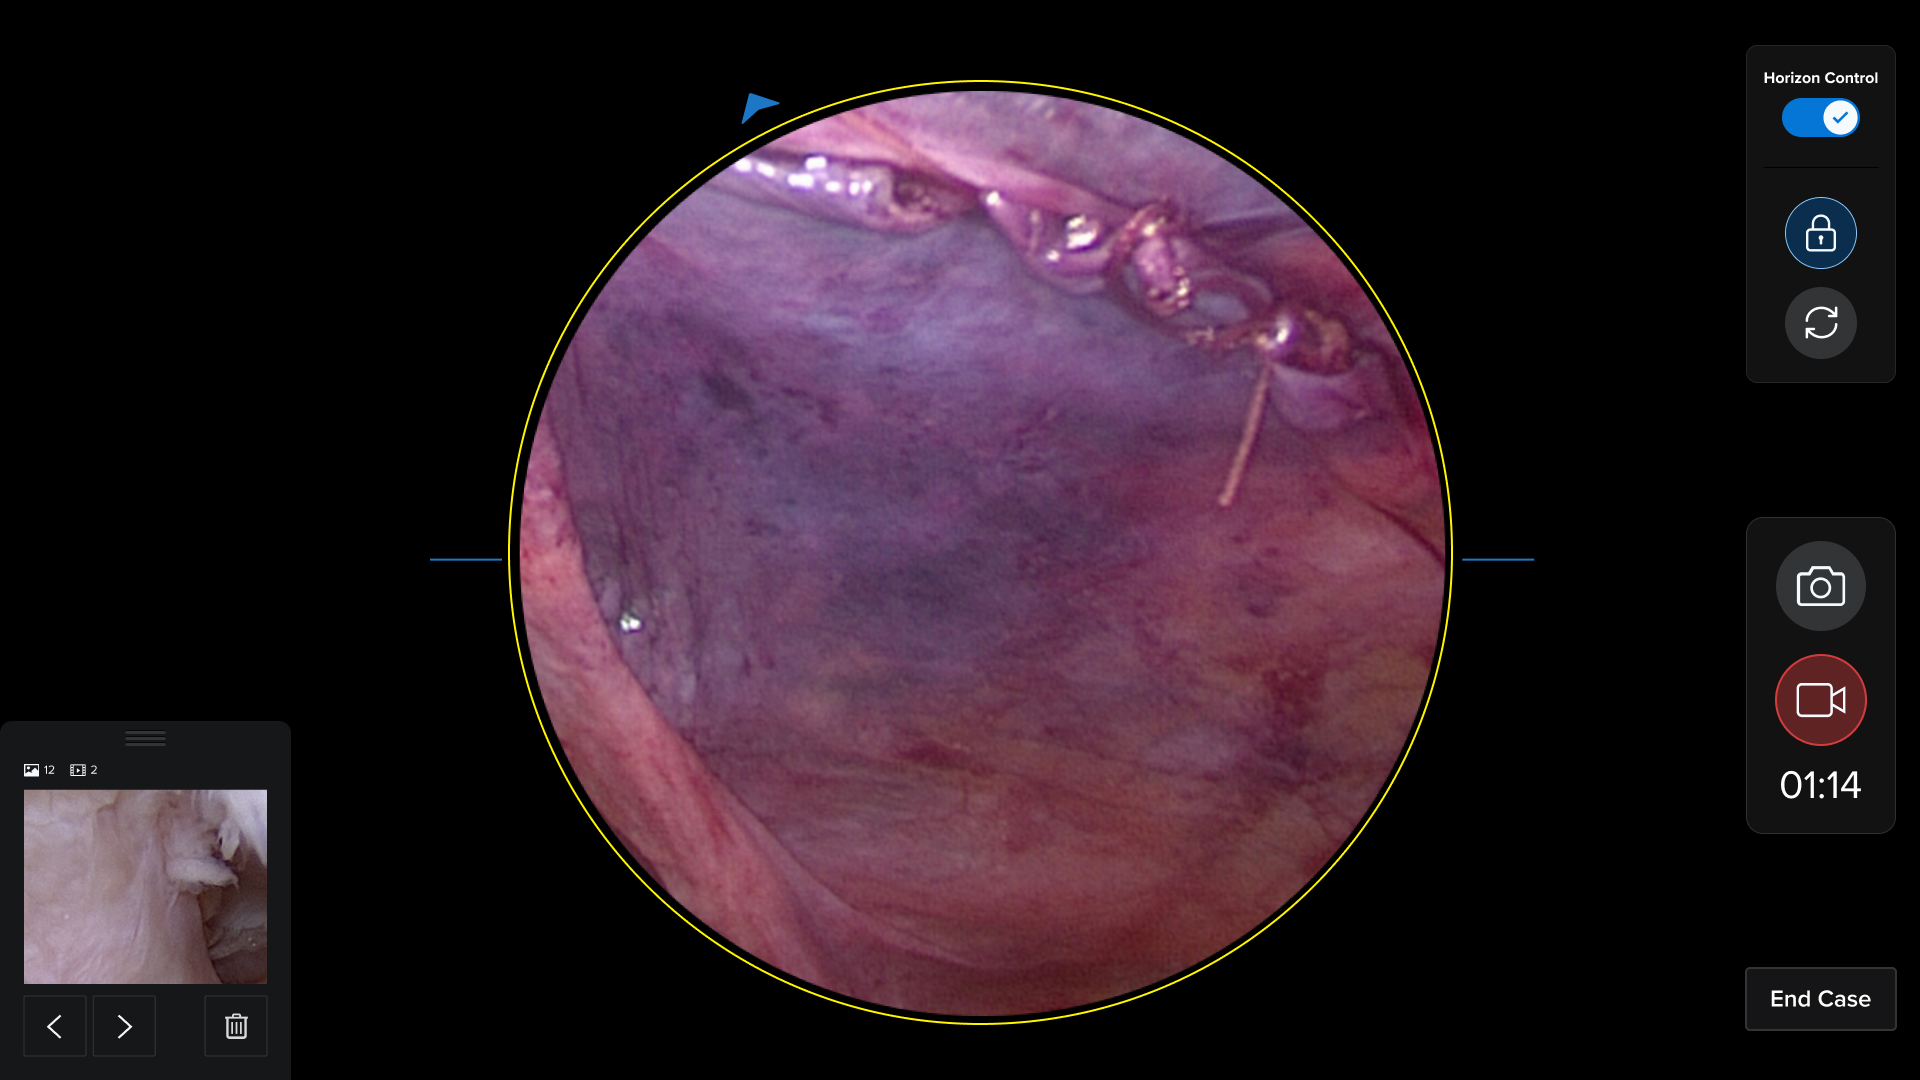

HUD Design: Surgery-Ready Interfaces

Operating rooms aren't like offices. I designed interfaces specifically for heads-up displays, considering lighting, distance, and the critical nature of surgical procedures.

- Created HUD displays that surgeons could actually use